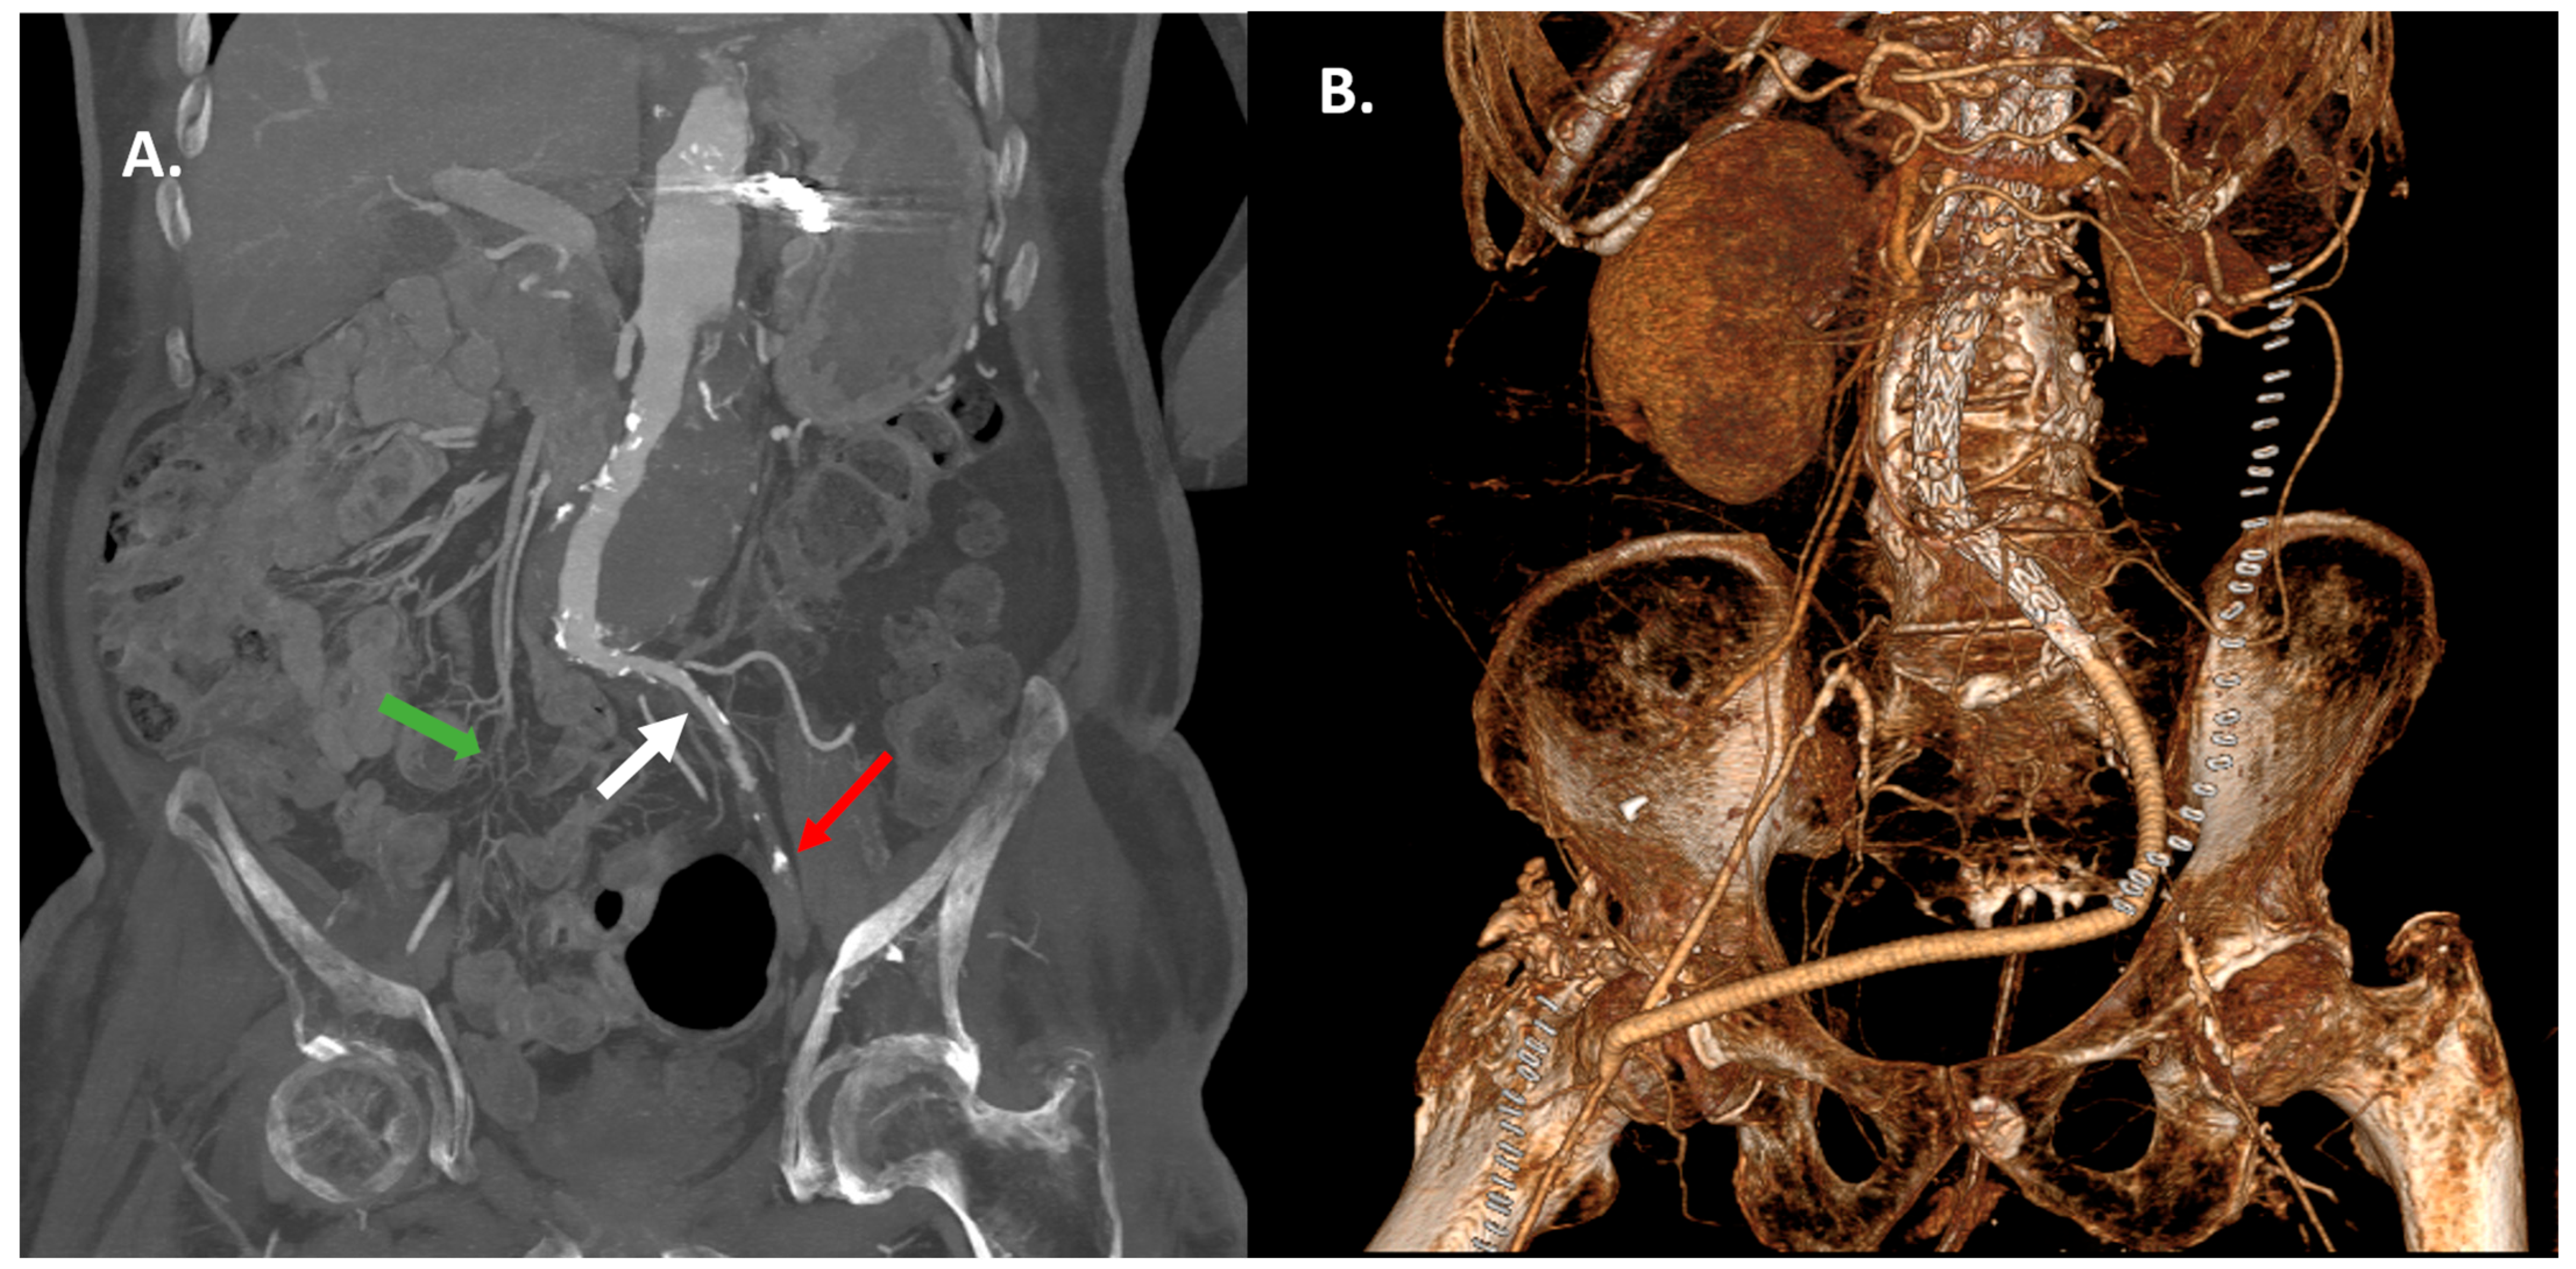

Open Iliac Conduits Enabling the New Era of Endovascular Aortic Repair in Hostile Iliofemoral Anatomy: A Single-Center Retrospective Study

| Iliac conduit position | Common iliac artery: n = 7 [87.5%] Aortic bifurcation: n = 1 [12.5%] |

| Reason for conduit placement | Small iliac artery < 7 mm: n = 3 [37.5%] Severely stenotic/occluded iliac artery: n = 5 [62.5%] |